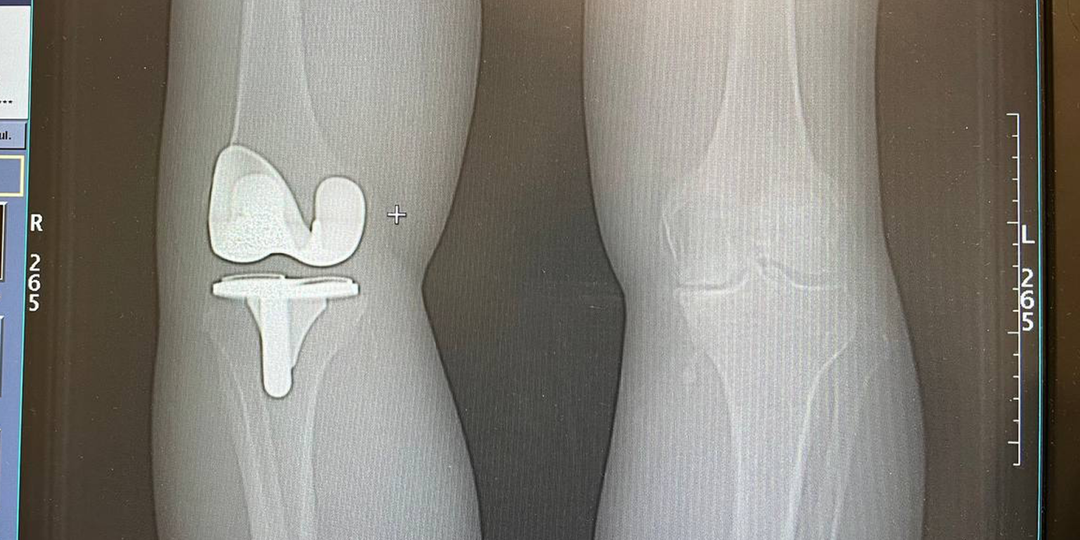

6 лет боли в колене — и одно решение, которое вернуло движение

Клинический кейс эндопротезирования коленного сустава Microport Medial-Pivot. Субвастус «Чаще всего пациенты приходят ко мне с одной фразой:

“Доктор, я уже всё перепробовал”.

Этот случай — как раз из таких». Меня зовут Исаев Максим Вадимович, я травматолог-ортопед Клиник СМТ.

Сегодня расскажу реальный клинический случай — эндопротезирование коленного сустава у пациента из Санкт-Петербурга, который шесть лет жил с болью и до последнего откладывал операцию. Если вы сомневаетесь, делать ли эндопротезирование коленного сустава, — этот материал стоит дочитать до конца. Первые симптомы появились ещё в 2020 году: Типичная история. На этом этапе большинство пациентов рассчитывают обойтись без операции — и это нормально. Пациент последовательно проходил консервативное лечение коленного сустава: Первые годы это действительно помогало.

Но затем эффект стал временным, а боль — постоянной. Со временем ситуация изменилась: Именно в этот момент пациент обратился к нам— уже с вопросом об операции